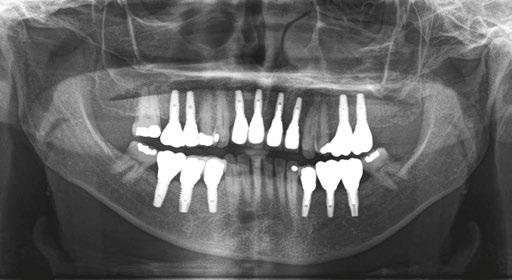

The patient returns four months later for a clinical follow-up (Figures 12A and 12B) and X-rays (Figure 13).

The permanent dentures are then placed over a titanium frame processed by Panthera Dental and stratified in composite at the denture laboratory (Figures 14A-14C).

Figures 12A and 12B: Clinical postoperative situation after 4 months Figure 13: Postoperative X-ray follow-up after 4 months Figures 14A-14C: Permanent denture (14A and 14B), intraoral view (14C)